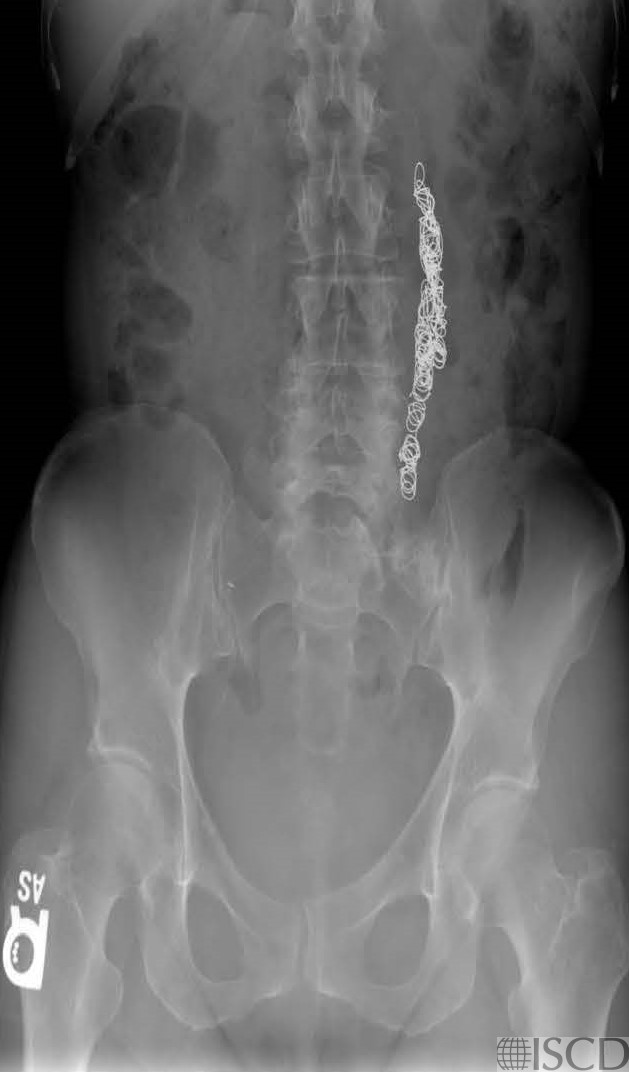

This is the accompanying abdominal radiograph showing the pelvic coils.

Pelvic coils are seen lateral to L2-L4 on the Hologic lumbar spine image. Pelvic coils are used for pelvic congestion syndrome. They are said to relieve pain by closing off faulty vein so they can’t become enlarged with blood. The coils show up as black hole-type artifacts.